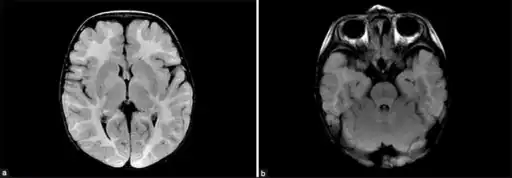

a,b) MRI of brain shows increased signal intensity -cortical/sub cortical white matter

MDDS is diagnosed based on systemic symptoms presenting in infants, followed by a clinical examination and laboratory tests (for example, high lactate levels are common) medical imaging, and usually is finally confirmed and formally identified by genetic testing.[5]